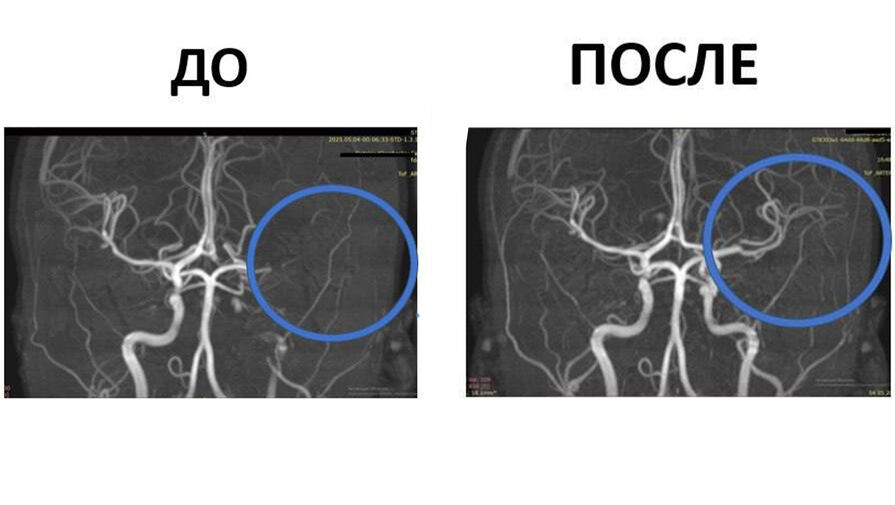

Бригада скорой помощи доставила ребенка в больницу. По словам матери, дочь принимала ванну, когда у нее онемели руки, лицо стало ассиметричным, а речь нарушилась. При обследовании выяснилось, что левая сонная артерия ребенка перекрыта плотным тромбом: у девочки произошел ишемический инсульт.

«Благодаря слаженной работе и оперативности родителей девочка оказалась в больнице через два часа. Мы провели тромболизис — медикаментозную процедуру для растворения тромба. Это спасло ребенка от тяжелой степени инвалидности», — рассказала заведующая отделением неврологии Нина Маслова.